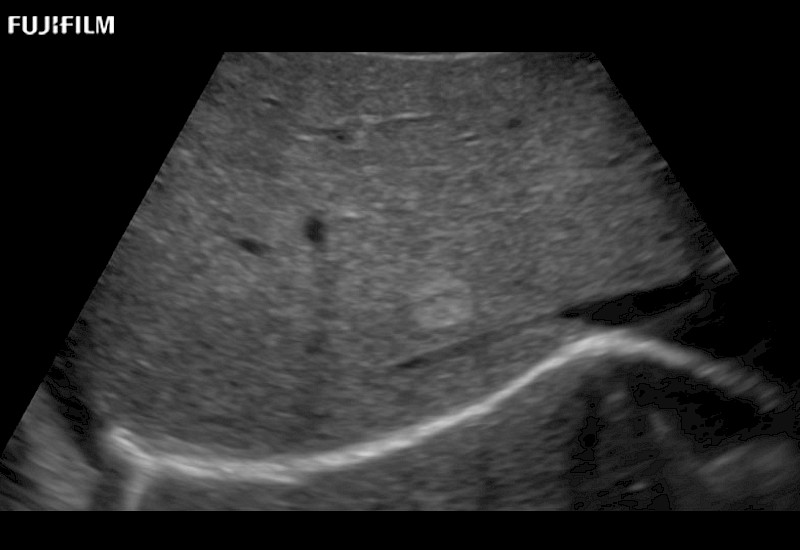

Extraordinary high-resolution digital imaging

- Exceptional near and far-field resolution

- Instant feedback on tumor margin delineation

- Valuable information to guide tumor resections

- Exceptional near and far-field resolution

- Instant feedback on tumor margin delineation

- Exceptional near and far-field resolution

- Instant feedback on tumor margin delineation